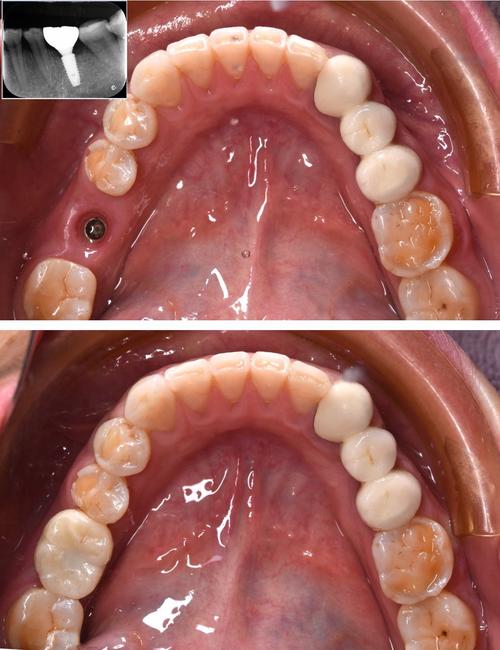

种植牙是通过外科手术将纯钛种植体植入牙槽骨内,模拟天然牙根,再在种植体上安装基台和牙冠,实现“仿生”修复的方式,被誉为“人类的第三副牙齿”,是目前修复牙缺失的理想方式之一。

- 种植体植入:局部麻醉下,切开牙龈,暴露牙槽骨,逐级备洞后植入种植体,缝合伤口;

- 骨结合期:种植体与牙槽骨通过骨整合融合,通常需3-6个月(即刻种植或骨条件好者可缩短);

- 基台安装与牙冠制作:骨结合完成后,安装基台,取模制作牙冠(全瓷冠、烤瓷冠),试戴调整后粘接或螺丝固定。